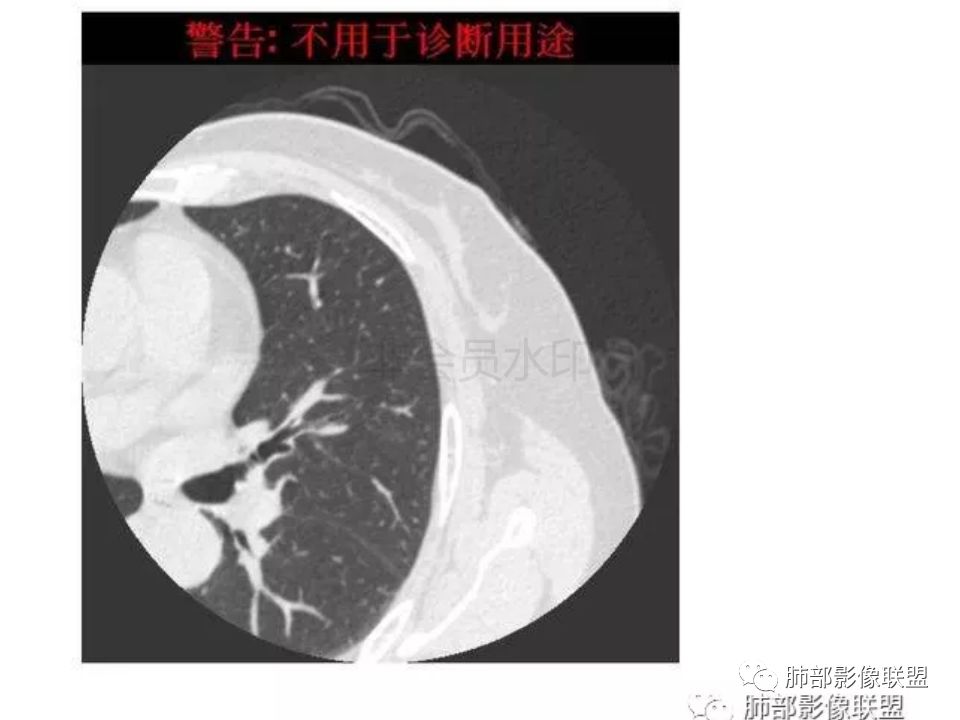

三生石上:支气管有截断,周围有晕,有空泡,腺癌?毛勤香:左肺下叶近胸膜下结节,周围磨玻璃影,边界似稍模糊,局部细支气管截断,实性区和磨玻璃区分界突然,隐约细毛刺,首先考虑感染性,隐球菌?待排腺癌MIA伴肺泡塌陷可能。常规治疗后复查。Coke with ice:IACM-Imaging :孤立胸膜下结节,其内见小泡,周围模糊的晕,晕中软毛刺,近端与血管相连,血管自然通过,气管进入结节内部一半,猜个隐球吧。第二腺癌,建议复查。田园晚风:考虑腺癌紫气东来:左肺上叶,磨玻璃实性毛刺,空泡,支气管截断,腺癌雪颜:左肺上叶结节状密度增高影,周围有晕,感觉周围模糊,有血管进入,里面有空泡征,隐约看到里面有支气管穿过,考虑炎性,隐球菌感染?腺癌待排THINKER:上叶尖后,SPN,有晕,软毛刺,无胸膜凹陷,分叶丶收缩不明显,支气管进入,远端阻塞,首选肉芽肿,PC或炎性结节,有一支血管滋养,鉴别腺癌,增殖性结核结节不支持期:左上肺结节周围有晕 晕中见细软毛刺 首先考虑隐球菌一米阳光:左肺上叶磨玻璃影,空泡,周围毛刺,月牙铲,支气管通过,周围有晕,考虑腺癌我的FY:毛刺,小空泡,磨玻璃考虑恶性崔少钢:小病灶,内有支气管,空泡征,实变不规则,放大了,感觉晕有点偏清,考虑恶性。小病灶里面有支气管是值得高度怀疑的。没有病史。彭君:左肺上叶舌段结节 周围晕模糊 内小支气管扩张 近端与血管相连 自然通过 首先考虑炎性 隐球菌?边缘月牙铲 腺癌待鉴别徐婕:左上肺结节周围有晕 ,晕中见细软毛刺 ,晕边界不太清,先考虑隐球菌张帅:左肺上叶尖后段实性病灶,以细支气管为中心,周围呈毛玻璃样影,并可见密集分布毛刺,内可见支气管征,支气管呈壁呈结节样改变,病灶周围可见血管增粗。考虑 淋巴瘤?鉴别隐球。张延军:混合型磨玻璃结节,伴毛刺,支气管截断,空泡,考虑浸润性腺癌,建议抗炎治疗后复查XGQ:支持隐球春秋:结节伴晕征,晕中毛刺,相邻小支气管近端进入,远端阻塞,近端血管相连,首先考虑隐球菌王秀仙:左肺上叶混合型磨玻璃结节,支气管截断,空泡,有毛刺,考虑浸润性腺癌,建议抗炎治疗后复查玫:左肺上叶磨玻璃结节影,薄扫见长短不一毛刺,有空泡,病灶边缘见晕征,考虑小腺癌可能,不除外炎性结节。zyf:左肺下叶近胸膜下结节,周围有晕,细软毛刺,有支气管进入,实性区和磨玻璃区分界明显,首先考虑感染性,隐球菌?查隐球菌荚膜抗原!RockJ-ason:考虑隐球采莲:左上肺靠近胸膜下实性结节影,边缘模糊,周围有晕及晕中毛刺,支气管进入通畅,有小空泡。考虑炎性病变,隐球可能性大。鉴别结核。Harvey:左肺下叶舌部小结节,边缘见磨玻璃影,边界欠清,内见支气管、管壁不光整,偏向恶性。鉴别隐球菌lmg:左肺上叶混合小结节,有晕,边界模糊,有有小毛刺。考虑炎性病变,隐球收选。AIS并肺泡塌陷带排。山河:倾向腺癌红日东升:GGO边界似清非清,内部好像不是小空泡,是小支气管腔,倾向炎性病变,常规抗炎复查除外腺癌,尤其粘液腺癌。

我怎么感觉支气管是通的,周围的晕又比较软,我考虑炎性病变,隐球菌可能大(如下图)

隐球菌感染孤立病灶与肺腺癌结节在影像上有时难分彼此,尽管隐球菌胸膜下更常见。

1.隐球菌病灶往往是实性密度结节为主伴周边边界不清楚的晕,有时可见晕内细软毛刺。

微浸润腺癌常常是磨玻璃密度为主的结节,边界比较清楚,并似乎有弧线形小叶间隔阻挡的痕迹。

实性结节的腺癌则很少有磨玻璃晕,往往会有粗短的硬毛刺。

2.隐球菌病灶形态往往圆钝柔和,缺乏收缩能力,很少出现腺癌的那种胸膜牵拉和棘状突起。

3.病灶内支气管安然无恙隐球菌病灶更加多见

4.隐球菌病灶增强扫描可轻度强化。既不同于结核灶的几乎不强化,也不同于肺腺癌的明显强化。

该患者实性成分为主,可惜未提供增强扫描图像。